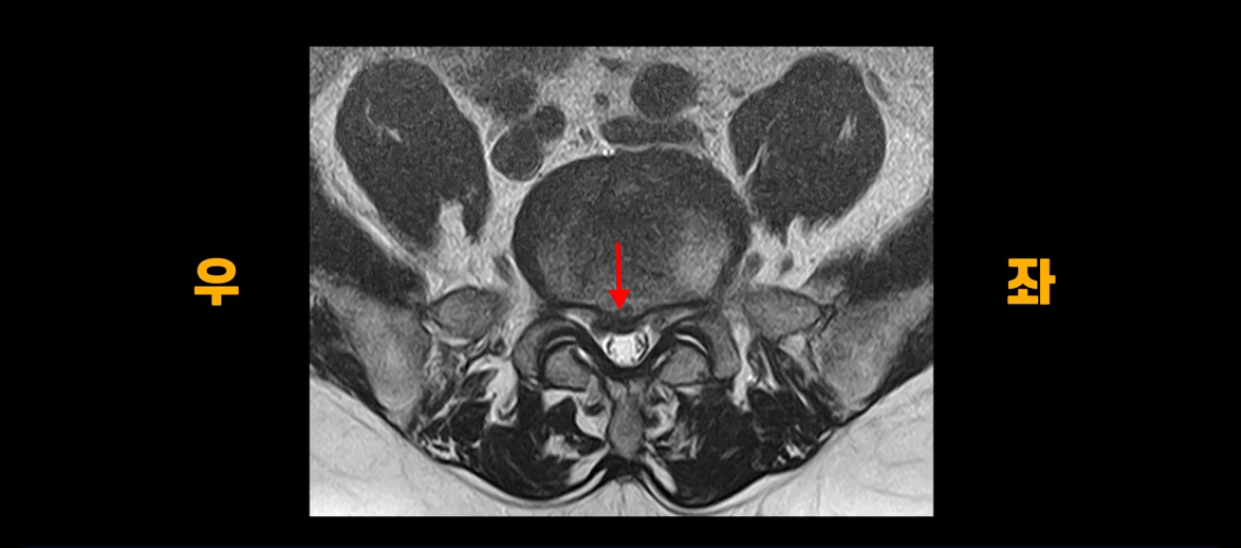

단면을 보면 중앙 오른쪽으로 밀려 나왔는데 파열이 아주 심하지는 않습니다.

아주 심한 상태가 아니라서 방사통만 있지 마비, 즉 힘 빠짐은 없는 상태입니다. 이 정도의 크게 심하지 않은 디스크 탈출 정도라면 신경 주사 맞고 버티다 보면 좋아질 수도 있지만, 이 환자분은 보존한 지 10개월 후에 증상이 더 나빠집니다. 왜 그럴까요? 신경 주사도 전혀 듣질 않는데 어떻게 해야 수술 없이 좋아질 수 있을까요? 지금부터 설명해 드립니다.

이분은 1월에 무거운 걸 들다가 허리디스크가 파열되고 방사통 증상이 나타난 후 10개월 동안 많은 허리디스크 환자가 하는 전형적인 보존 치료 방법을 따라 합니다. 신경 주사, 신전 운동, 허리 구부리지 않기, 걷기 운동 등 이런 방법들을 열심히 하면서 무려 10개월의 시간을 보내지만, 방사통은 오히려 더 악화됩니다. 그 이유는 뭘까요? 저희가 수많은 설명 영상, 치료 후기 영상을 통해서 방사통으로 아픈 사람들이 몇 달씩 버티다 보면 몸이 다 틀어져 버린다고 말씀드렸습니다. 몸이 뒤틀리게 되면 한 달 정도면 가라앉아야 할 신경의 염증이 가라앉지 않고 흡수가 되어야 할 밀려 나온 디스크 수핵도 흡수가 안 된다고 설명해 드렸습니다. 다리 한쪽이 아프니까 안 아프려고 몸을 하루 종일 비틀고 있는데 거기다가 신전 운동하고 신전 자세 한다고 허리에 힘을 주고 있고, 허리를 구부리지 않으려고 하루 종일 허리를 뻣뻣하게 하고 있으니까 허리가 완전히 굳어버리면서 몸이 뒤틀리는 겁니다.